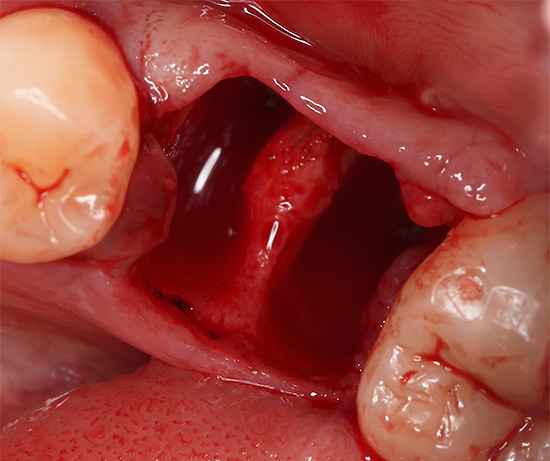

Depois que o cirurgião dentário extrai o dente do buraco, começa o processo de cicatrização da ferida pela chamada intenção secundária. Isso significa que o ligamento circular ao redor do dente se contrai e as bordas das gengivas se juntam. A formação de um coágulo sanguíneo no poço tem um efeito muito benéfico no processo de cicatrização de uma ferida após a extração do dente - esse coágulo desempenha um papel importante como um tipo de proteção contra possíveis infecções. Consequentemente, em nenhum caso você deve remover esse coágulo, por exemplo, lavando intensamente a boca ou, principalmente, mecanicamente - com um dedo ou um palito de dente.

O coágulo sanguíneo é substituído por tecido de granulação por vários dias e, em seguida, é formado tecido osteóide. Em outras palavras, com o tempo, um novo osso com uma gengiva formada acima dele se forma no lugar do dente extraído.

Com a extração traumática do dente, quando a gengiva se rompe e uma parte significativa das paredes do buraco é danificada, o processo de cicatrização pode demorar muito tempo e o tempo necessário para restaurar o tecido dependerá de vários fatores.